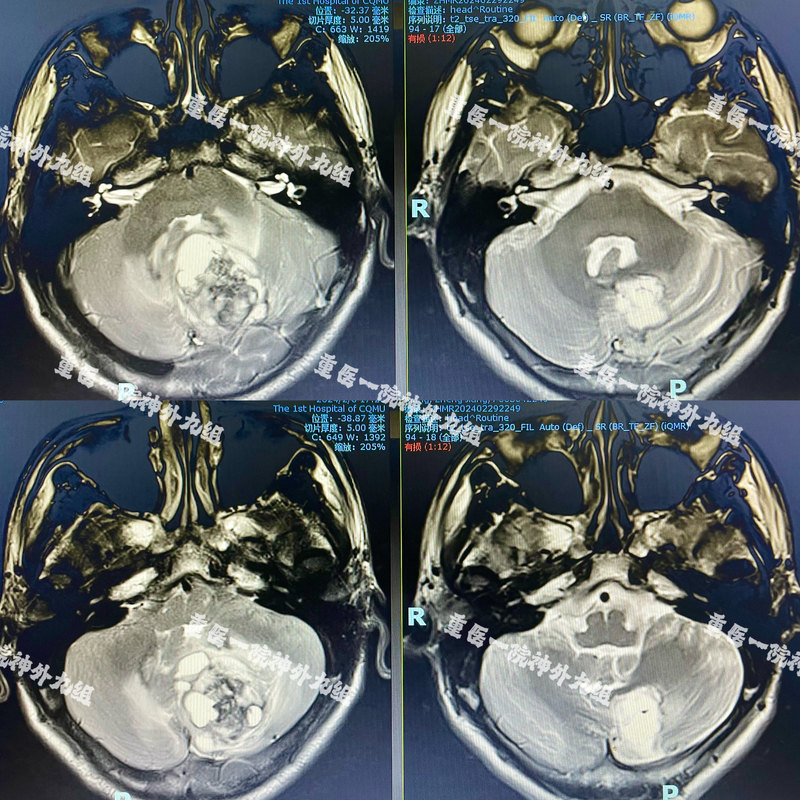

后顱底是神經(jīng)外科患病的高危部位。后顱底腫瘤不但引起頭痛、嘔吐等高顱壓癥狀,嚴(yán)重者誘發(fā)枕骨大孔疝等嚴(yán)重后果,治療不及時有猝死可能。春節(jié)前最后一個工作日,夏海堅主任醫(yī)師團(tuán)隊收治一急診病患,該患者系護(hù)理專業(yè)的在校大學(xué)生,因頭痛進(jìn)行性加重二月、頻繁惡心嘔吐一周入院?;颊呒韧鶑奈吹结t(yī)院正規(guī)就診,急診MR顯示左側(cè)小腦半球及蚓部巨大占位性病變,已經(jīng)存在枕骨大孔疝影像表現(xiàn),病情極危重,若再有耽擱,則隨時有腦疝致死可能(圖1)。病情就是生命,需要爭分奪秒。夏海堅主任醫(yī)師在年前最后一個工作日緊急安排腫瘤切除術(shù)。經(jīng)過手術(shù)、神經(jīng)電生理和麻醉團(tuán)隊的通力合作,術(shù)中顯微鏡下全切腫瘤。術(shù)后患者高顱壓癥狀得到奇跡般緩解,恢復(fù)順利。且術(shù)前合并的梗阻性腦積水得到一期緩解,達(dá)到了“一箭雙雕”的效果,無需再次手術(shù)(圖1)?;颊呒凹覍倬o縮的雙眉終于得到了舒緩。年后隨診時送上錦旗一面,表達(dá)了對于重獲健康的感謝之情(圖2)。重醫(yī)附一院神經(jīng)外科作為首批國家臨床重點??坪椭貞c市神經(jīng)外科質(zhì)控中心,具有悠久的歷史和優(yōu)秀的傳承。感謝各位病員朋友們的信任,我和我的團(tuán)隊將繼續(xù)竭盡全力,為您的健康努力。